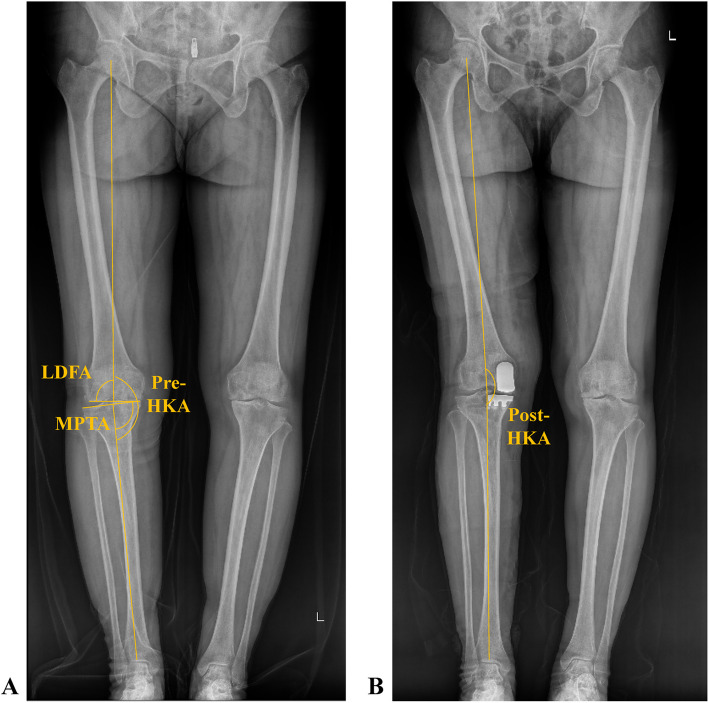

Methods: A retrospective analysis was conducted on individuals who received medial UKA at a specialized orthopedic hospital between January 1, 2024, and July 31, 2024. The aHKA was determined using the formula: medial proximal tibial angle (MPTA) minus lateral distal femoral angle (LDFA), plus 180°. The relationships between the postop HKA angle and the aHKA, MPTA, and LDFA were analyzed. Patients were further divided into three categories based on their postop HKA angle: greater than 180°, between 175° and 180°, and less than or equal to 175°. These groups were then compared in terms of aHKA, LDFA, MPTA, and preoperative HKA angle.

Results: A total of 242 patients (254 knees) were included in this study. The postop HKA was nearly equal to the preoperative aHKA (176.09° ± 2.86° vs. 176.23° ± 3.15°). Statistical analysis revealed a positive association between aHKA and postop HKA angle (R2 = 0.4595, P < 0.05), as well as between MPTA and postop HKA angle (R2 = 0.2072, P < 0.05). Conversely, a negative correlation was identified between LDFA and postop HKA angle (R2 = 0.2448, P < 0.05). These patterns held true for both fixed-bearing and mobile-bearing UKA prostheses. Notable differences among the three HKA groups were found regarding aHKA, MPTA, LDFA, and preoperative HKA angle (P < 0.05).